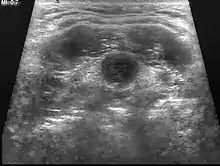

L’échographie est l’examen de choix car facile d’accès, peu coûteux et non irradiant (en particulier chez l’enfant). Elle retrouve une masse arrondie, anéchogène, aux parois lisses. Elle vérifie également la bonne position de la thyroïde.